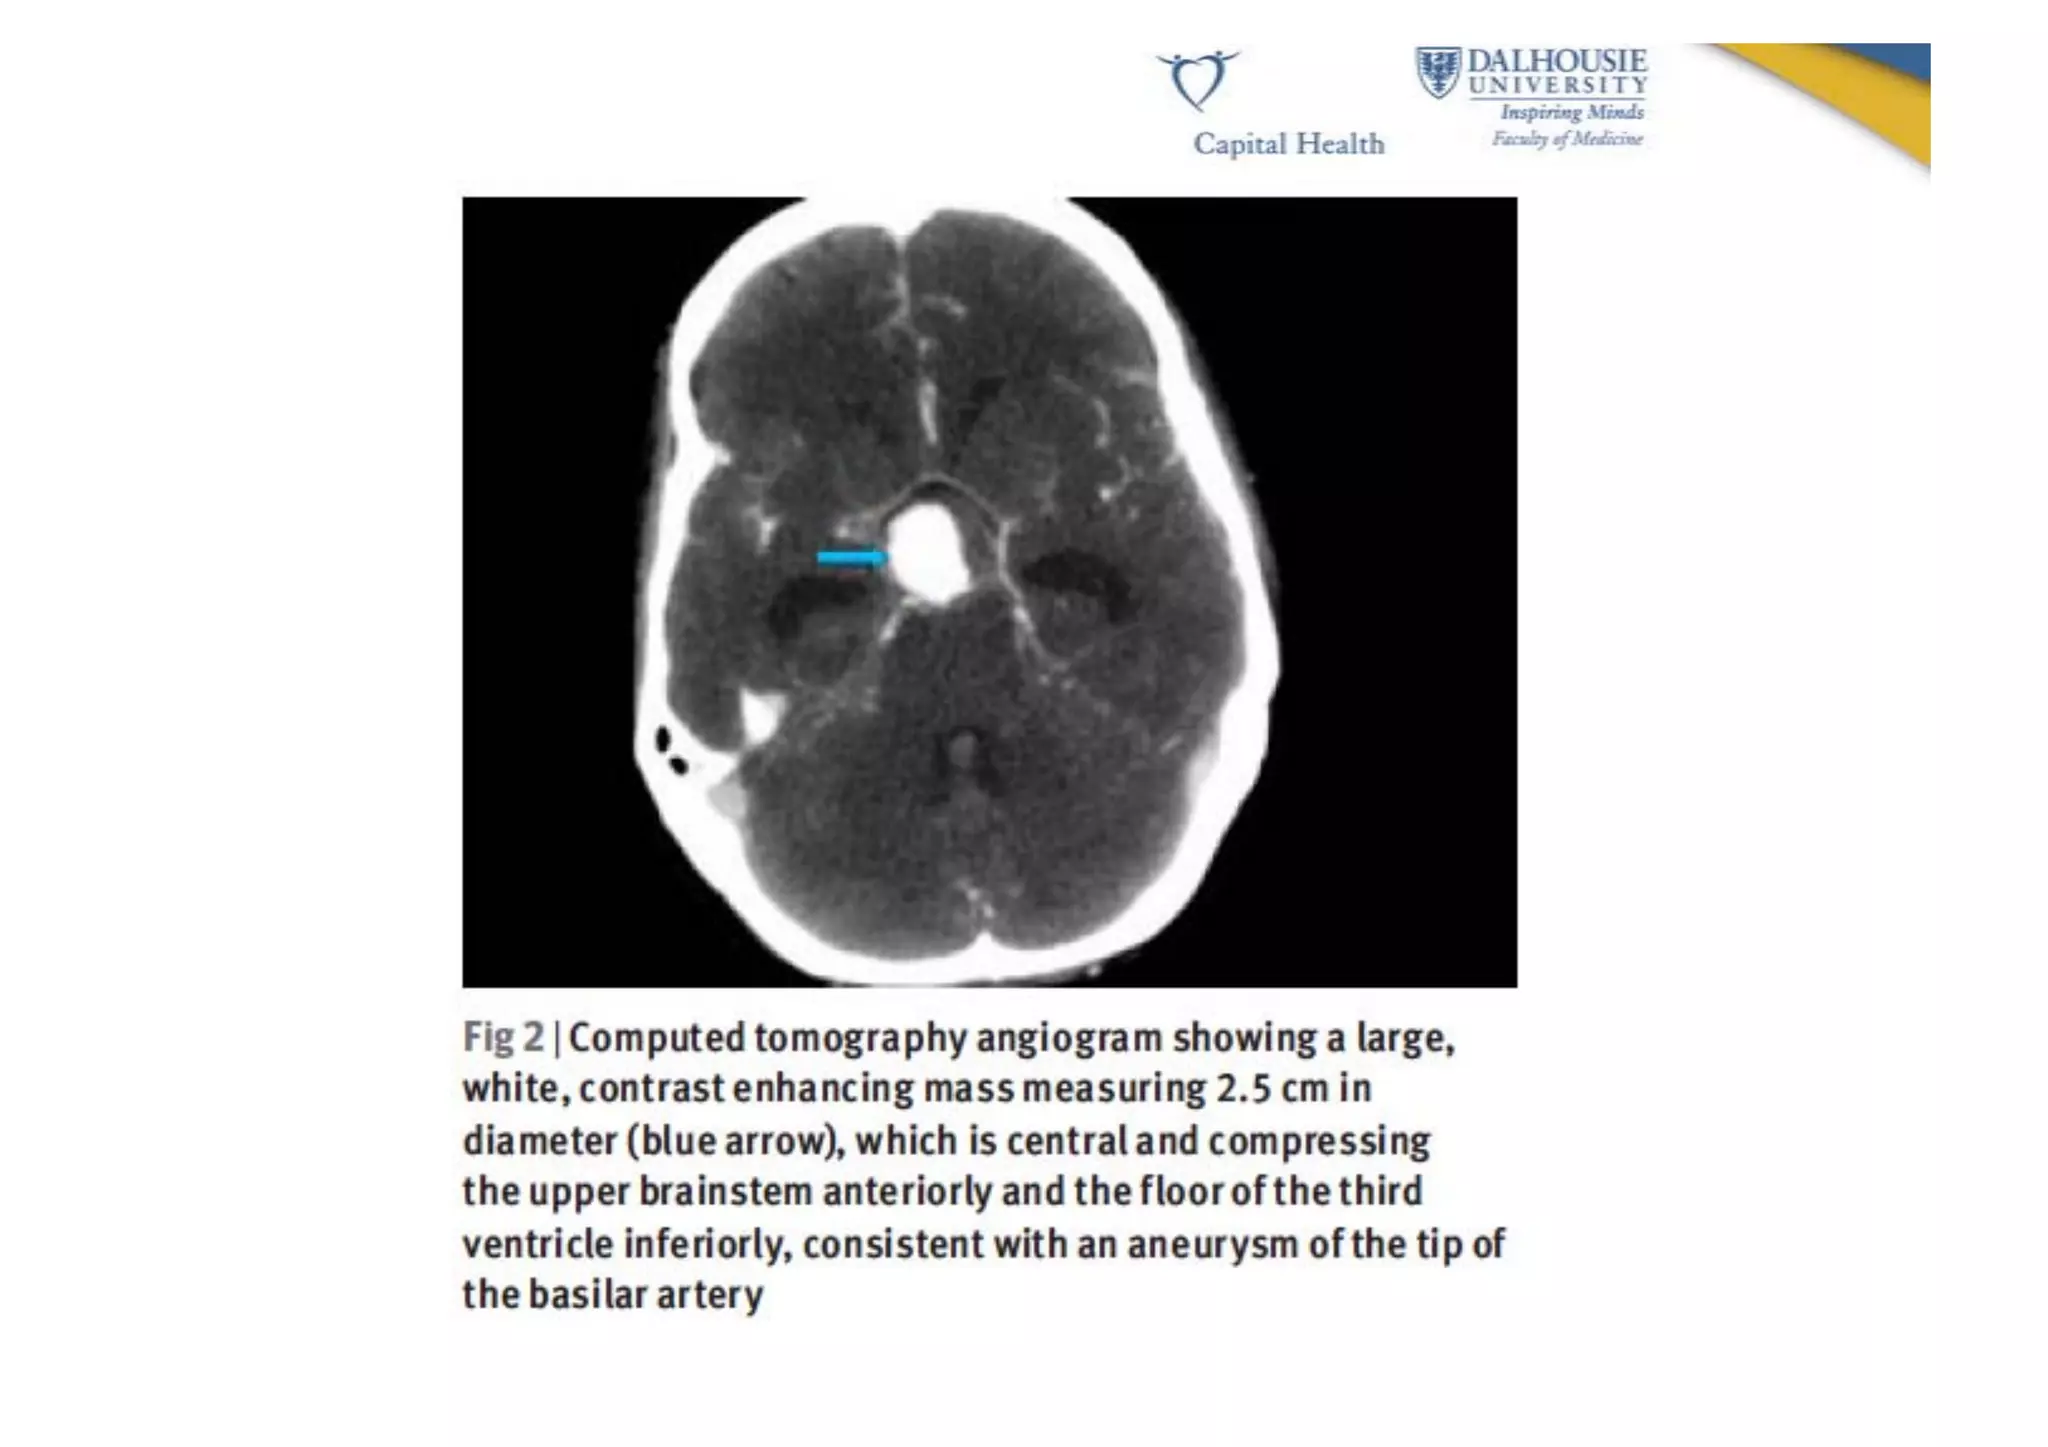

Diagnosis   •  CT  scan  AND  lumbar  puncture  if  scan  is  nega9ve   •  If  SAH  is  found,  it  is  usually  followed  with   catheter  cerebral  angio  or  MR/CT  angio  to   document  the  anatomic  features   •  CT  scan  detects  93-­‐98%  of  SAH